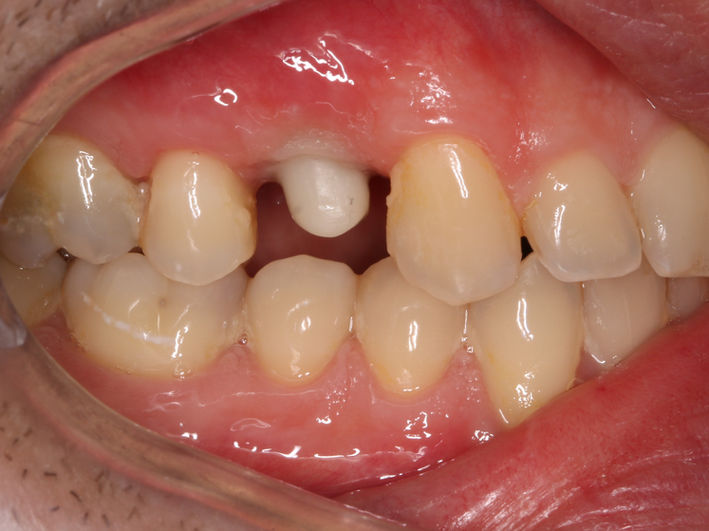

1. Tratamentul caninilor incluși

Caninii incluși sunt acei dinți care nu erup în poziția corectă în cavitatea bucală, rămânând incluși în os sau gingie. Această problemă este destul de frecventă și poate afecta atât estetica zâmbetului, cât și funcția de masticație.

Incidența caninilor incluși variază în funcție de populație și de studiu, dar, în general, se estimează că aproximativ 1-2% din populație este afectată de această problemă. Caninii superiori sunt mai frecvent incluși decât cei inferiori.